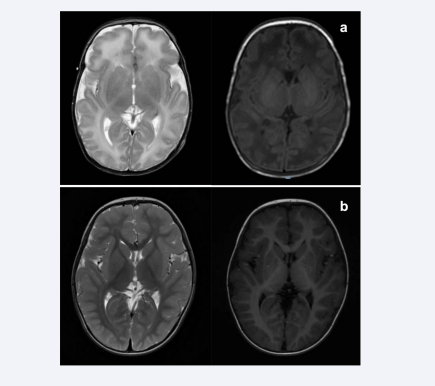

Brain magnetic resonance imaging (MRI) performed at 19 days of age showed elevated T2 signal in the white matter, slightly higher T1 signal in the globus pallidus, and blurred long T1 signal in the posterior limbs of the internal capsule [Figure 2a].

Figure 2 (a) Brain magnetic resonance imaging (MRI) performed at 19 days of age showed elevated T2 signal in the white matter (left), slightly higher T1 signal in the globus pallidus, and blurred long T1 signal in the posterior limbs of the internal capsule (right). (b) Re-examined brain MRI at the age of 2 years was normal.

Figure 2: (a) Brain magnetic resonance imaging (MRI) performed at 19 days of age showed elevated T2 signal in the white matter (left), slightly higher T1 signal in the globus pallidus, and blurred long T1 signal in the posterior limbs of the internal capsule (right). (b) Re-examined brain MRI at the age of 2 years was normal.

To date, the boy has been followed up for 2 years. He is taking oral vitamin B6 at a dose of 10 mg/kg.day without any ASM. There were only 3 episodes of febrile convulsion at 1-year-old. His mental and motor development was mildly delayed, and his muscle tone was slightly low. However, after rehabilitation, he is now able to walk alone and speak several words. At the age of 2 years, his re-examined EEG and brain MRI were normal [Figure 2b].